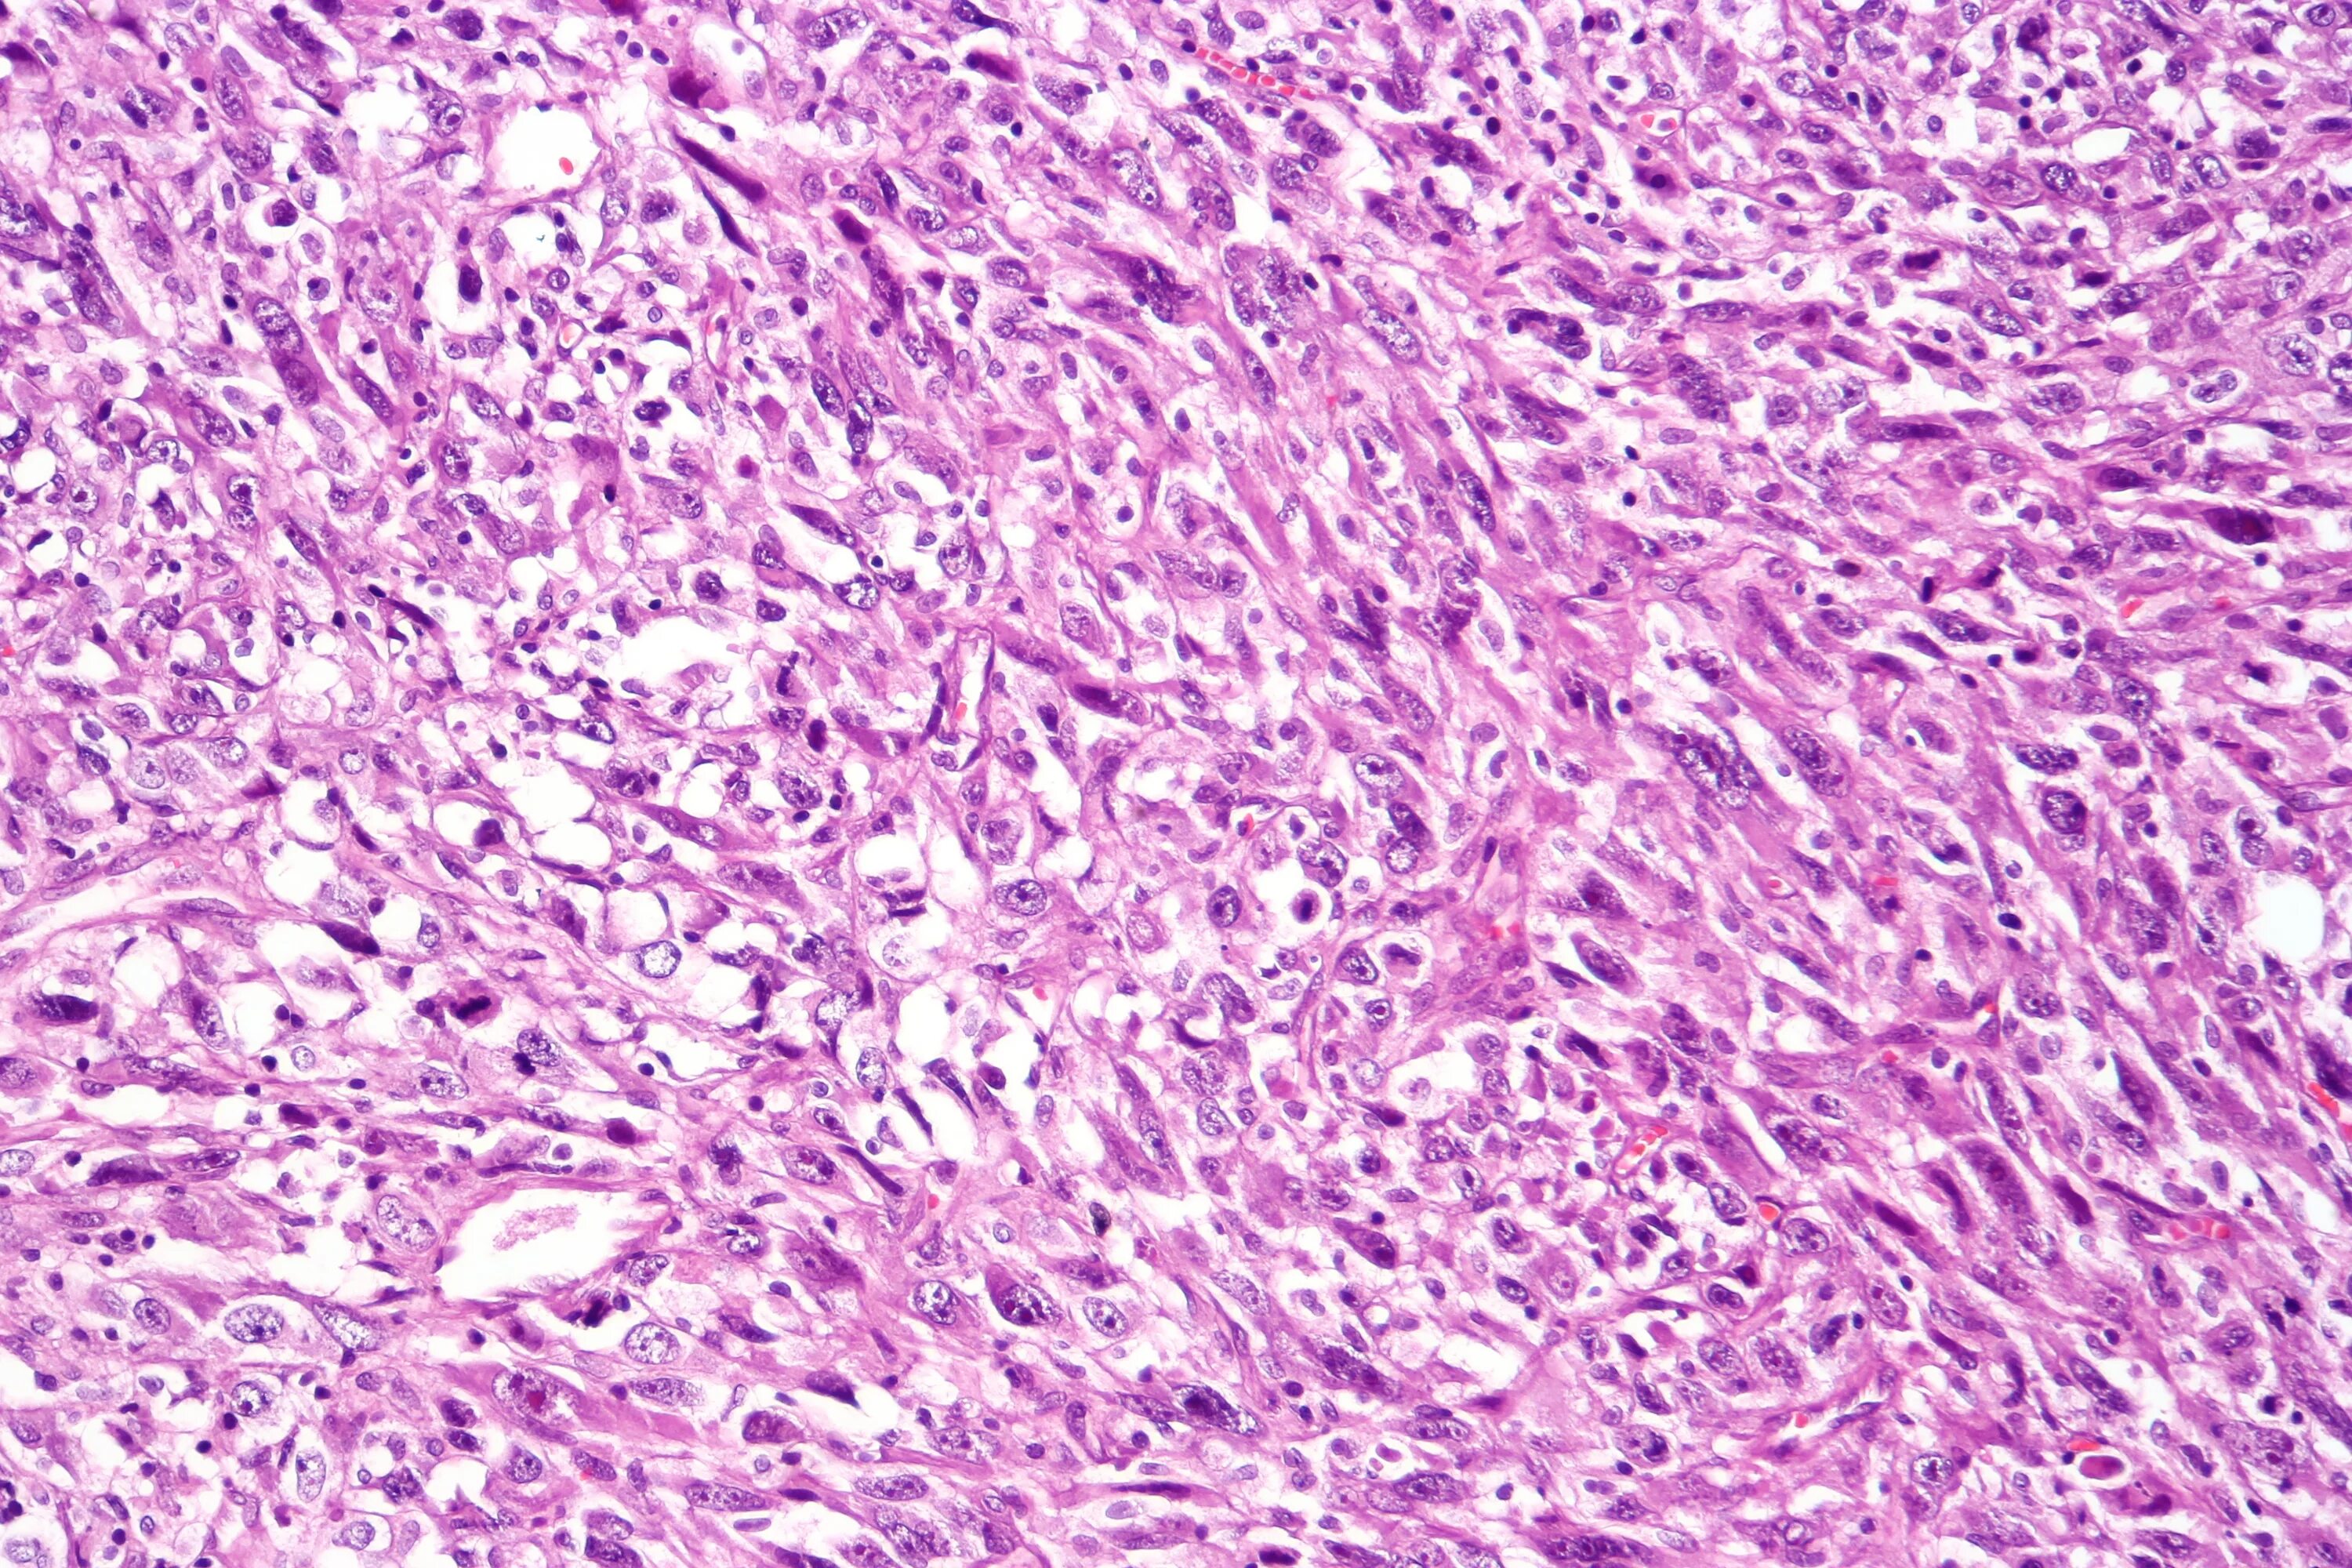

Гистологические варианты